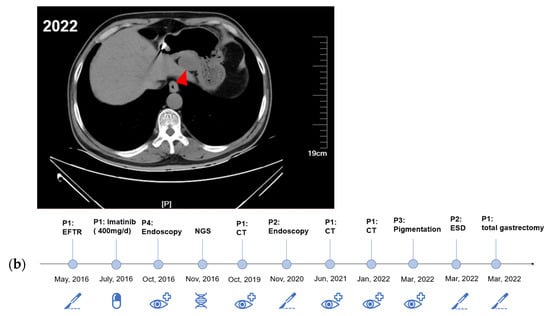

During the follow-up period, the proband was regularly evaluated by CT. Comparing the CT images from 2019, 2021, and 2022 (Figure 2a), the proband was found to have enlarged gastric subepithelial lesions (the largest tumor progressed from 2.5 cm to 3.8 cm in diameter). Other multiple exophytic growing gastric nodules were also found during enlargement by endoscopy. Considering the progression of diffuse gastric lesions, the proband underwent a total gastrectomy in 2022. The gross specimen of the proband showed multiple diffuse extraverted stromal tumors in the entire stomach (Supplementary Figure S2). The proband’s niece also showed progression of the gastric lesions, so ESD was performed. A schematic of the diagnosis and treatment strategy timeline for this family is presented in Figure 2b.

Figure 2.

The diagnostic and therapeutic process of this family. (a) CT showed continued progression of the proband’s GISTs (red arrows). (b) The overall timeline of the entire follow-up process.